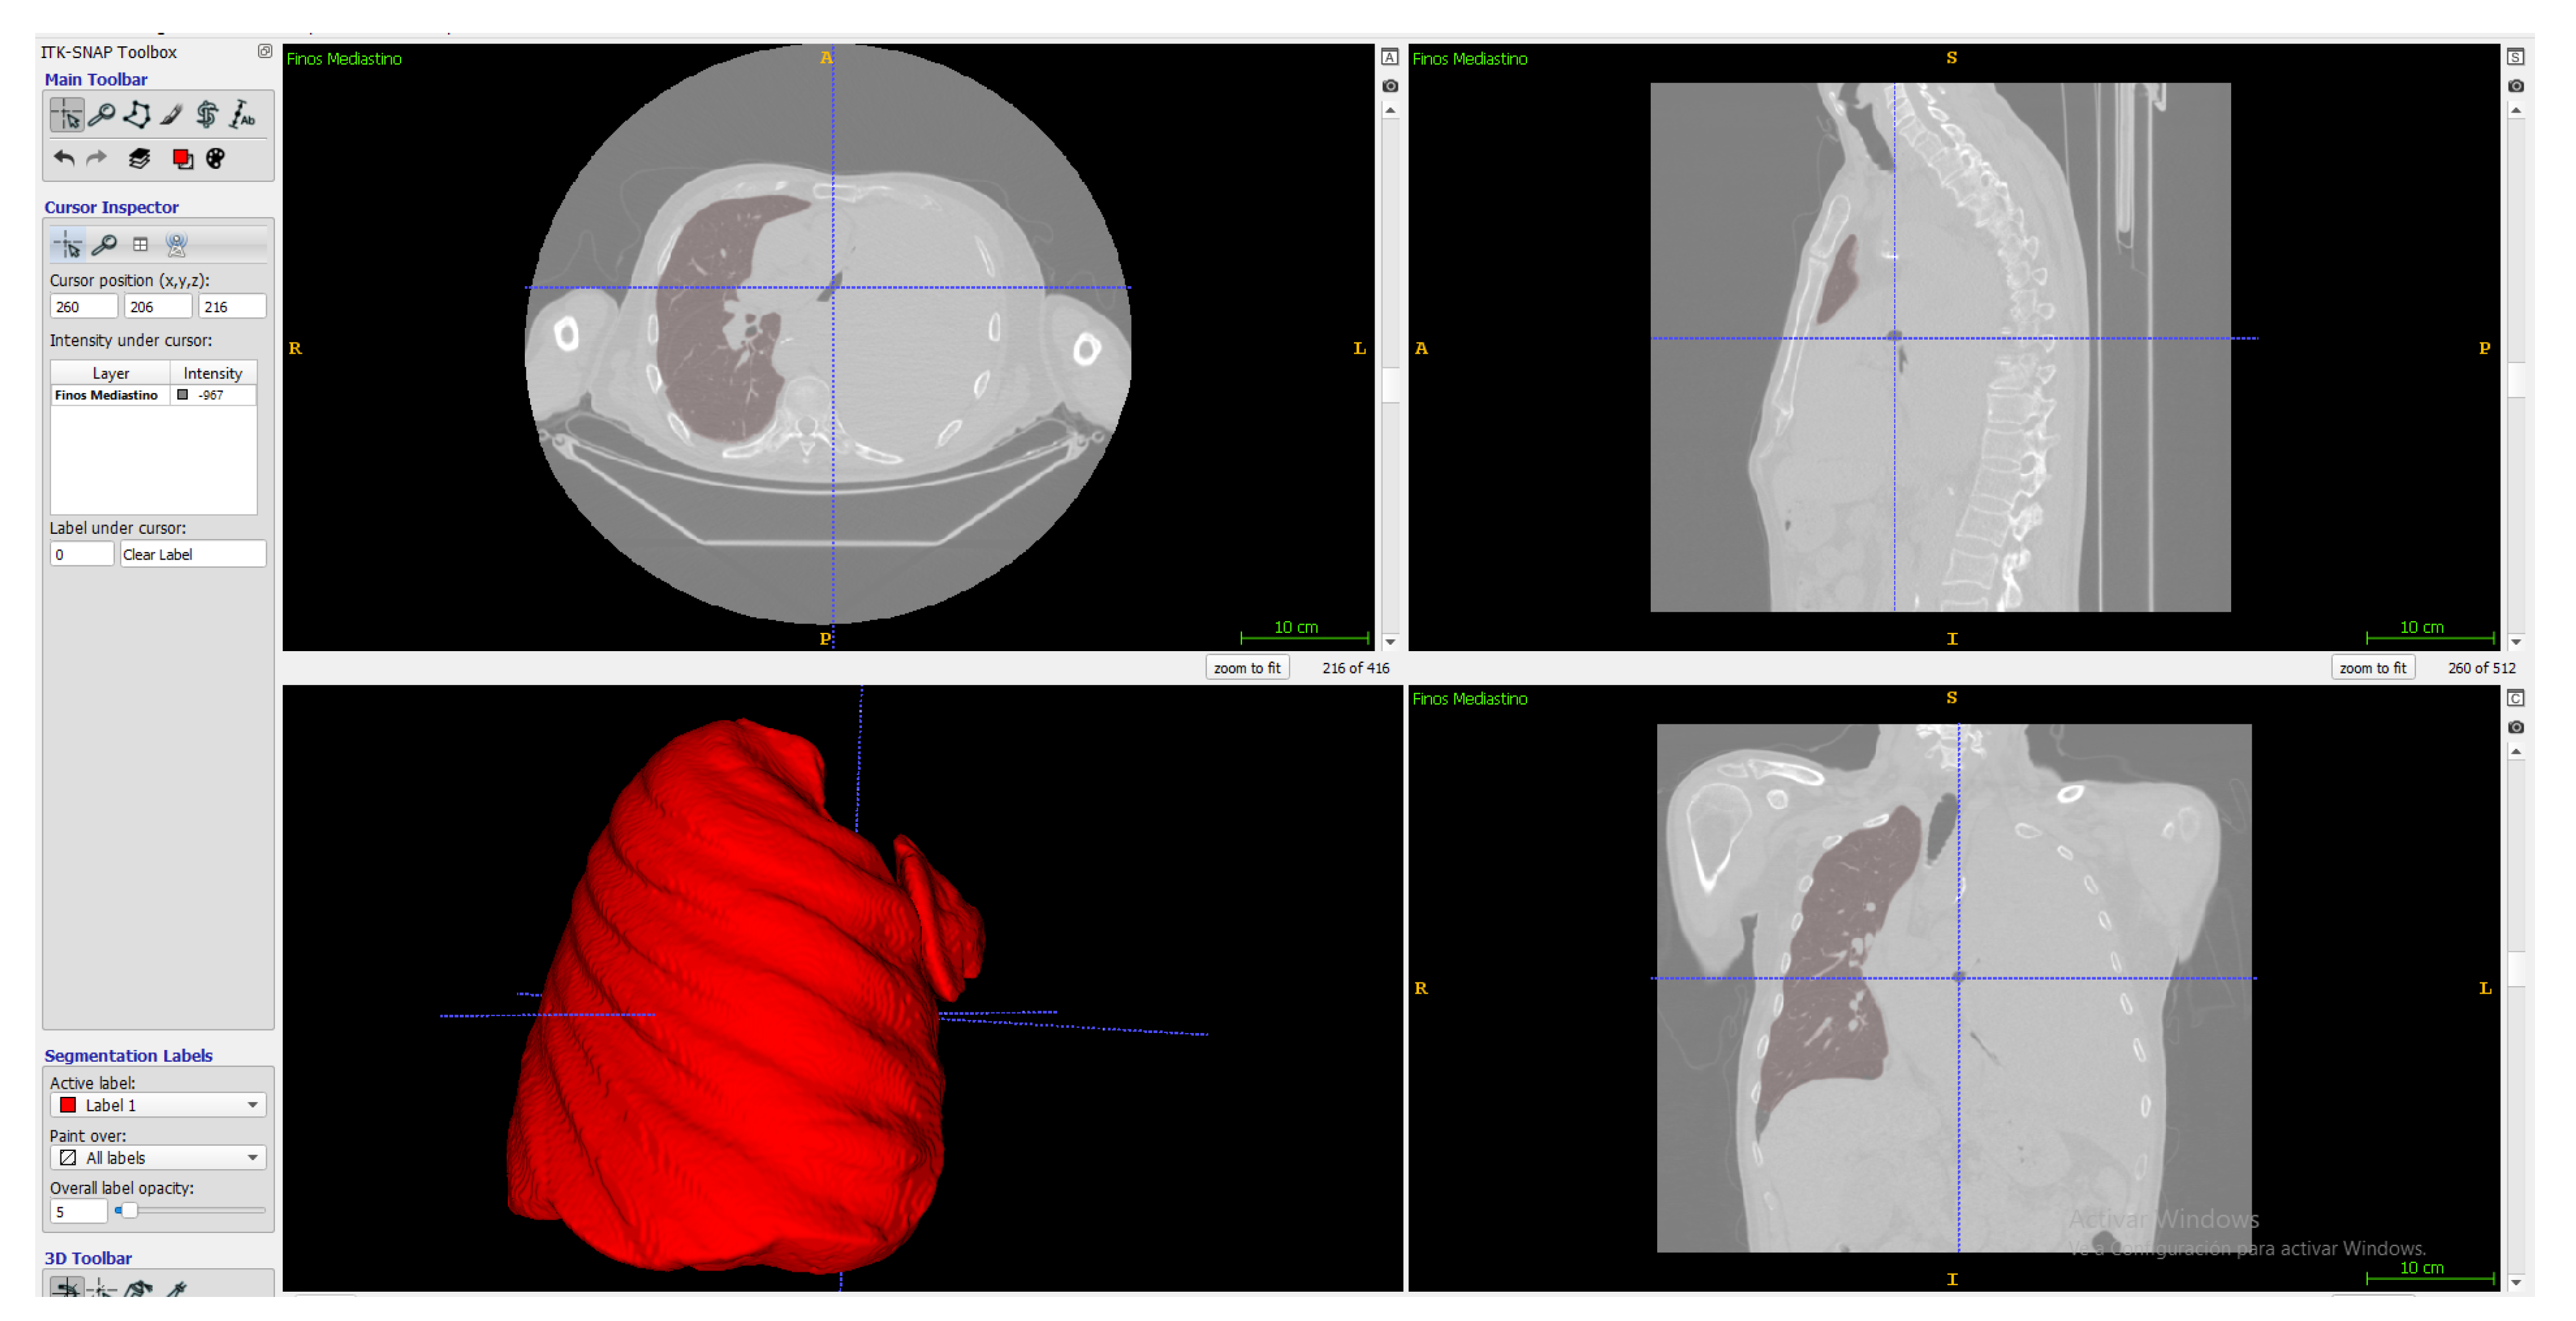

2.3.3. ITK-Snap

2.4. Tumor Segmentation Process